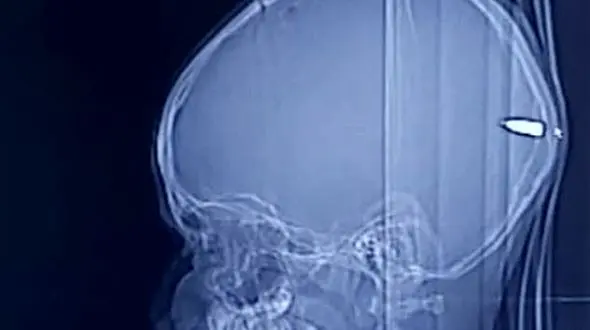

حوادث رکنا:پسر ۹ ساله فلسطینی که یک گلوله به پشت جمجمه اش اصابت کرده بود به جای مردن دچار خواب آلودگی شدید شد.